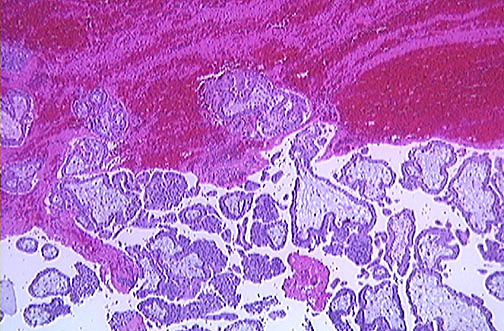

| Sometimes blood clot and chorionic villi, as seen here, are recovered outside of the tube following rupture of an ectopic pregnancy. Other sites of ectopic implantation include ovary, abdominal peritoneum, and cornual (uterine) portion of fallopian tube. |